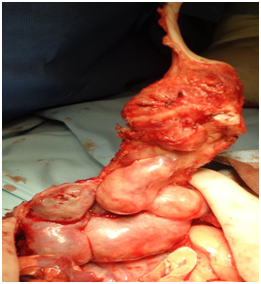

Extrapleurar excision of the mass was performed under general anesthesia. The excision involved the 6th, 7th and 8th ribs on the left from the costovertebral junction to costosternal synchondrosis FIGURE (3). The pleura was left intact. The remaining cartilaginous ribs were anchored to the adjacent intact ribs by 0.2 polyglactin 910 absorbable sutures in order to minimize the size of the post-operative wall defect. The muscles were approximated using 0.3 polyglactin 910 absorbable sutures and “dura mater” substitution from bovine collagen absorbable membrane, stabilized by 0.4 polyglactin 910 absorbable sutures on the remaining tissues as a substrate for the muscle development. During the postoperative period, the neonate required NICU monitoring for 3days Figures 4a-4d. Paradox respiratory chest wall movement was noted during this time but it was not associated with any signs of respiratory distress of the neonate. The cardiorespiratory tests were normal and the neonate’s post-operative course was uneventful. She was dismissed on the 8th post-operative day in good condition. The tumor on histology presented chondroid tissue with endothelium lined vascular spaces, osteoclastic giant cells and osteoid in keeping with immature mesenchymal lesion.

Figure 4b Intraoperative view of the lesion. Note that the affected tissues are solid and capsulated.

Figure 4c The excisioned lesion concerned in full length of the affected ribs.